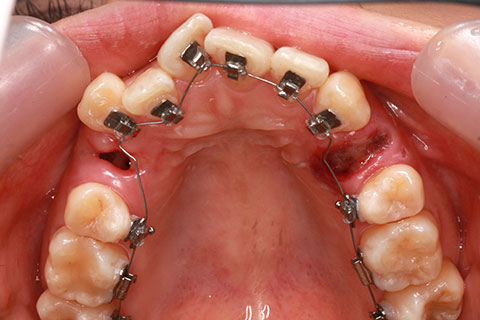

矯正期間18ヶ月

フルリンガル矯正2(上下の歯を舌側矯正で治療)

治療前

治療中

治療後

- 年齢・性別

- 42歳男性

- 治療期間

- 1年6ヶ月

- 抜歯

- なし

- 治療費

- 120万円(税込み)

- 備考

- マルチブラケットを用いた矯正治療

- 治療内容

- 反対咬合をフルリンガル矯正治療にて改善

- 施術の副作用(リスク)

- 表側矯正と比較して、歯根の角度を確立する「トルク」の力がかかりにくい。